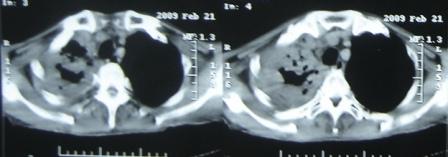

xx 男 63岁 发热 家属描述有时高热 有时低热 抗酸杆菌阴性 于2月21号 胸片及ct

3月10号复查